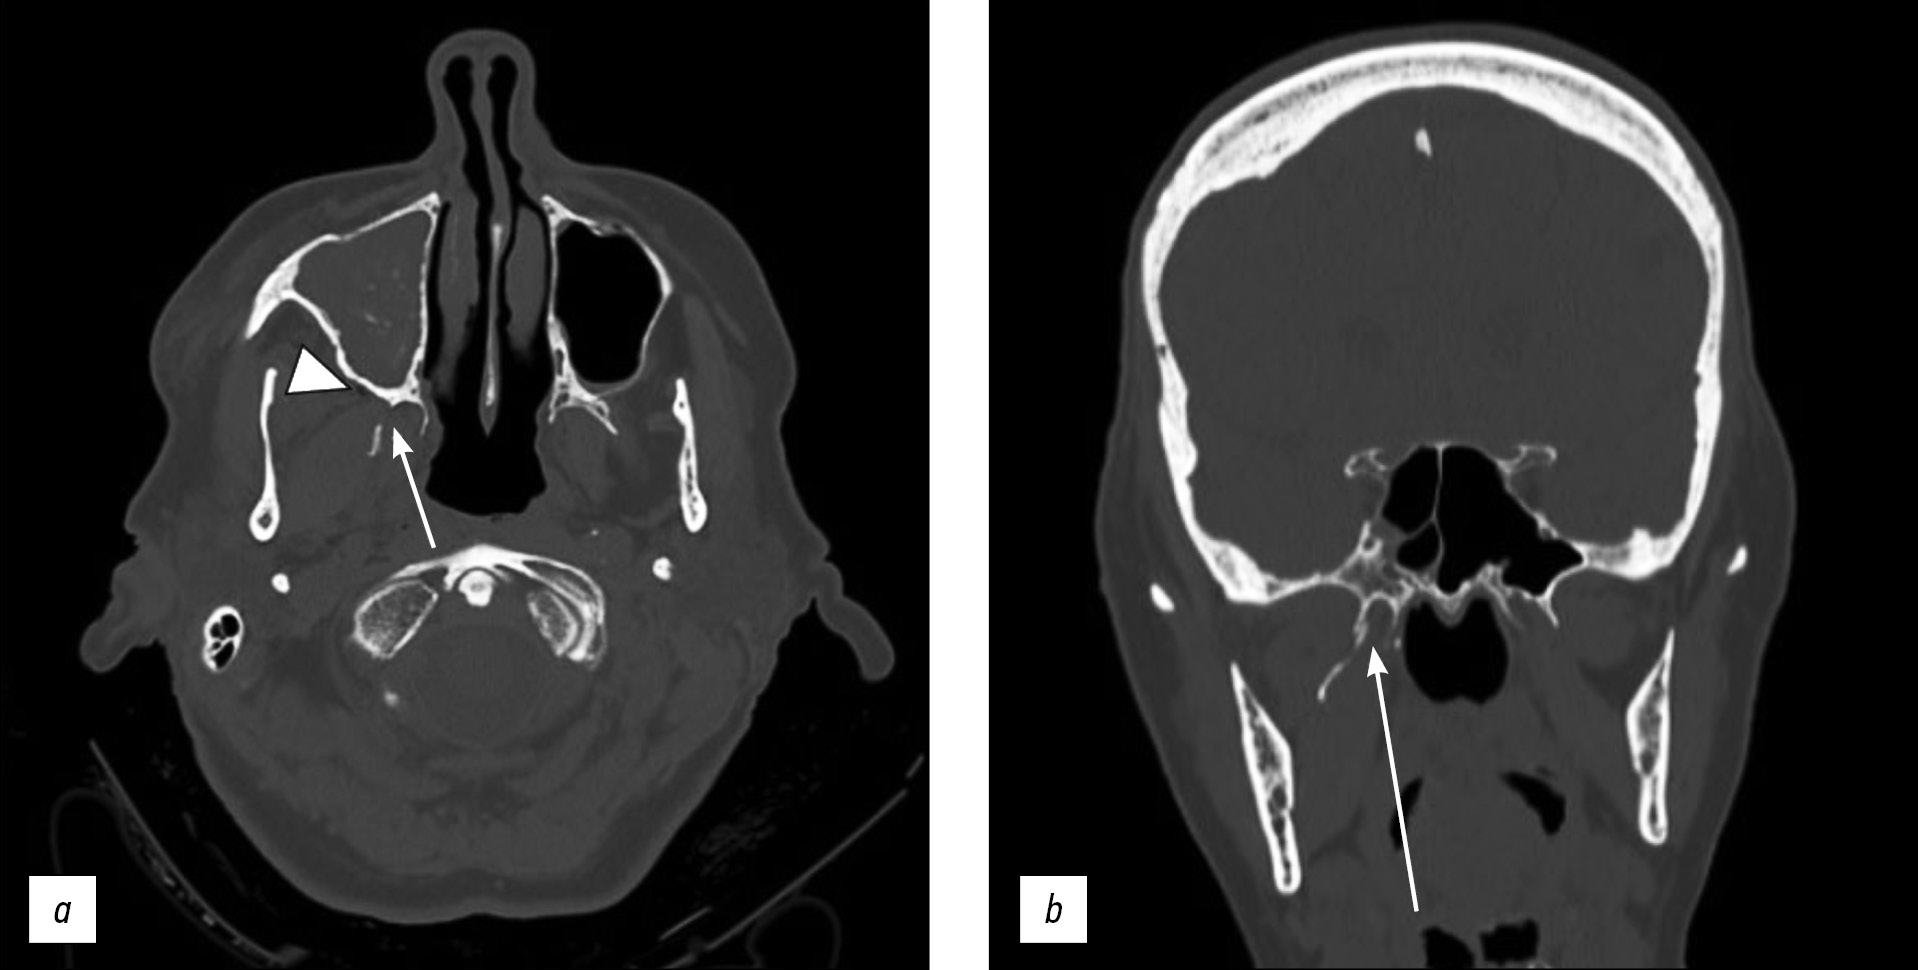

Unilateral isolated fracture of the pterygoid plate: a case report

Abstract

Pterygoid plate fractures are often associated with Le Fort fractures and accompanied by other facial fractures such as frontal sinus and naso-orbital-ethmoid fractures; isolated pterygoid plate fractures are extremely rare.

Le Fort fractures must be surgically treated with fixation of unstable fracture segments to re-establish bone form and function, and the pterygoid process must be surgically stabilized; however, surgical treatment is unnecessary in isolated pterygoid plate fractures.

Here, we report a rare case of isolated unilateral fracture of the pterygoid process in a 71-year-old female patient who had a syncopal episode with secondary head injury and a hematoma at the base of the right orbit.

A computed tomography scan showed unilateral right pterygoid plate fracture with signs of emphysema in the ipsilateral masticatory space. The patient also had a fracture of the medial wall of the right maxillary sinus with hemosine, but no fractures of the skull base or theca. She was treated conservatively.

71-77